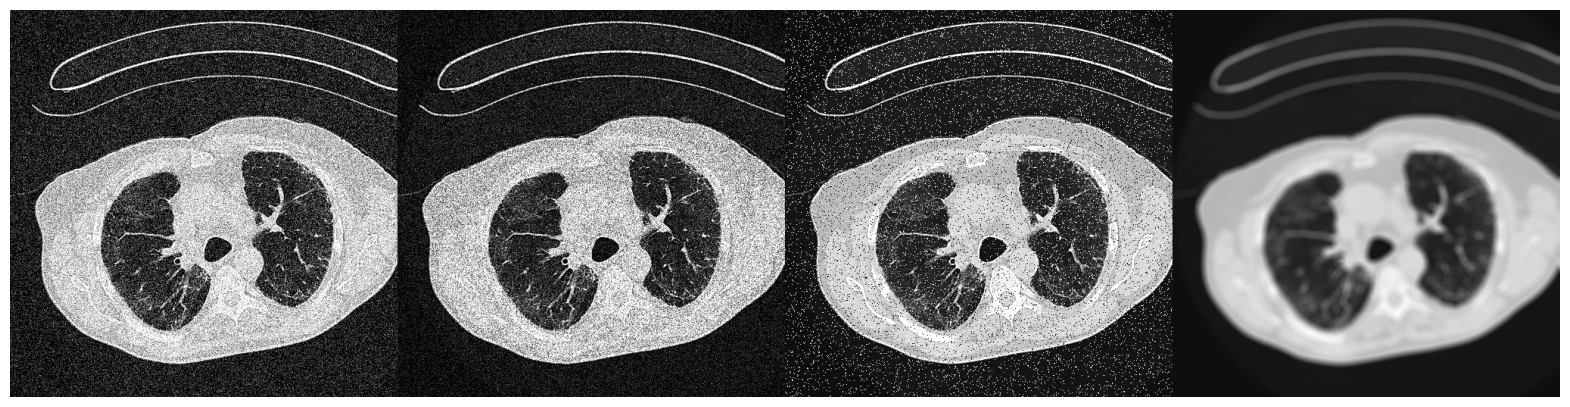

6.5.3 Validation with LUNG

The LUNG dataset is a collection of axial view lung CTs from three sources. The training and validation set consists of approximately 4000 slices extracted from 111 patient CT volumes from Pulmonary Fibrosis Progression (PFP), with their ground truth lung masks available in “CT Lung & Heart & Trachea segmentation” in Kaggle. We adopt another 90 axial view slices of lung CT volumes from “COVID-19 CT scans” showing lung with pneumonia as naturally occurring OOD data. (Access details in Section 4) The difference in the appearance of the COVID slices from the training set results not only from different imaging parameters but also from different infections. Each image is processed to have dimension 256×256256256256\times 256. We report below the mean IOUs and SBI of models trained on different models.

Training set IOUvalsubscriptIOU𝑣𝑎𝑙\mbox{IOU}_{val} IOUnoisysubscriptIOU𝑛𝑜𝑖𝑠𝑦\mbox{IOU}_{noisy} IOUOODsubscriptIOU𝑂𝑂𝐷\mbox{IOU}_{OOD} SBI

No Augmentation 0.982 0.938 0.962 2.650

Color Jitter 0.978 0.935 0.962 2.954

NST 0.978 0.941 0.962 3.014

Sep. Color Jitter 0.977 0.917 0.956 2.650

Negative Insertion 0.981 0.931 0.953 3.022

Random Resized Crop 0.942 0.793 0.853 2.534

Random Crop Reflect 0.979 0.672 0.943 2.128

Table 6: Performance of models trained on datasets with different augmentations when applied to the validation set, dataset with noise injected, and dataset with naturally occurred domain shifts for LUNG

.

Unlike in BFGT and FISH, as shown in Table 6, augmentations have much smaller effects on the performance of LUNG models. All augmentations that preserve targets’ shape yield models with very close performance on Validation, Noisy, and OOD data. Despite this, the effects of augmentations on SBI still align with our assumptions. Again, Random Resized Crop and Random Crop Reflect yield models with smaller SBI than the baseline, while the remaining augmentations increase each model’s SBI.

Refer to caption

(a) Image from "OSIC Pulmonary Fibrosis Progression" [38, 39]

(b) Image from "COVID-19 CT scans" [40, 41, 42]

(c) The image from "OSIC Pulmonary Fibrosis Progression" with (from left to right) Gaussian noise, shot noise, impulse noise, and defocus blur applied.

Figure 14: Samples from the three partitions of data domain in FISH

Augmentations, however, have negligible effects on this dataset. We explain this phenomenon by arguing that non-shape features may persist across multiple domains for LUNG. In LUNG, pixels associated with the lung have a texture style easily distinguishable from those associated with the rest of the image. The cooccurrence of high-intensity contours formed by cartilages also helps locate the lung. These features persist even across different image domains. In this case, the shape may not be the best discriminative feature in prediction capability. Non-shape features may be the more desirable feature sets to learn when optimizing the Cross-Entropy objective function. To avoid overstretching on interpreting the results, we will stop here with the conclusion that though Color Jitter and NST may suppress non-shape features, they barely hurt a model’s generalizability on Noisy and OOD data.